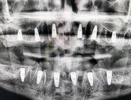

تسوس الأسنان

فقدان الأسنان

أمراض الأسنان واللثة